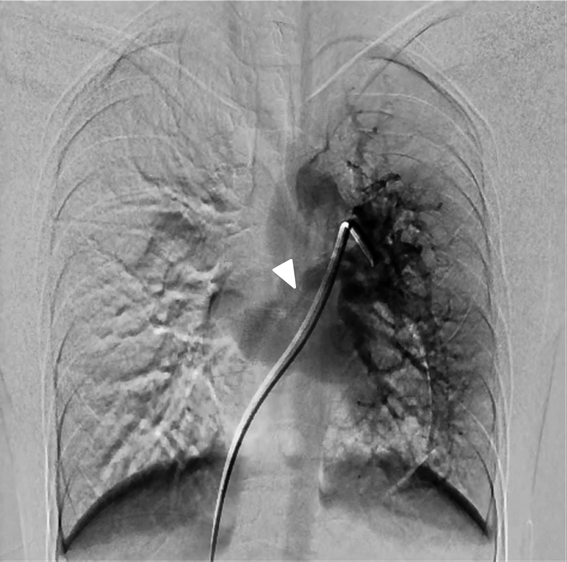

先天性片側肺静脈狭窄に対側のAnomalous Unilateral Single Pulmonary Veinを合併した1例A Case of Congenital Unilateral Pulmonary Vein Stenosis with Contralateral Anomalous Unilateral Single Pulmonary Vein